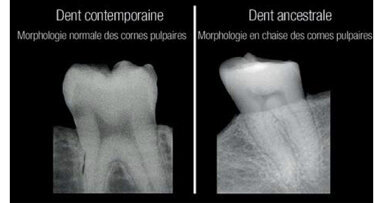

Hamilton, Ontario, Canada : les dents humaines conservent des informations vitales sur la carence en vitamine D, et des anthropologues canadiens ont à ...